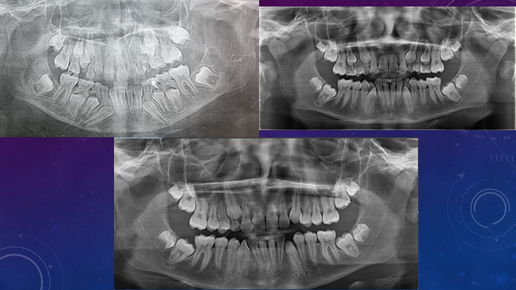

Из чего состоит ортодонтическое обследование и зачем оно нужно? 1 часть!

Зачастую пациенты врача-ортодонта задают себе (и не только) вопрос: зачем доктор назначает столько обследований? Наверное рентген-кабинет с ним делится?! Поставил-бы брекеты, да и всё!

Ортодонтия. Что это и зачем?

Ортодонтия- это раздел стоматологии, изучающий и занимающийся лечением дефектов зубочелюстной системы...